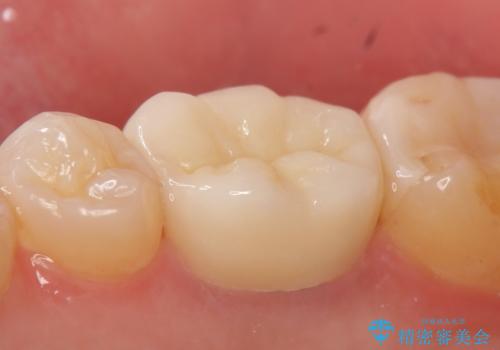

症状が治まったのを確認後、オールセラミッククラウンによる補綴を行いました。

今回用いたオールセラミッククラウンはジルコニアフレームという白い素材の上にセラミックを盛っているため、審美性が非常に高いのが特徴です。

また、ジルコニアは人工ダイヤモンドの材料にも使われているほど高い強度を持っており、そのためオールセラミッククラウンは審美性だけでなく、奥歯やブリッジの補綴も可能とするクラウンです。